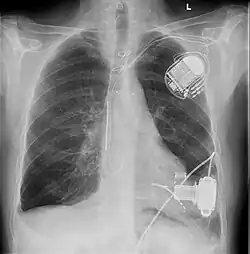

Ein Kunstherz oder künstliches Herz (auch Herzunterstützungssystem, ventricular assist device VAD, und Ventrikuläres Unterstützungssystem genannt) kann in den Körper von Patienten mit unheilbaren Herzerkrankungen (z. B. Herzinsuffizienz) eingesetzt werden, wenn das Herz des Patienten nicht mehr in der Lage ist, den Körperkreislauf ausreichend aufrechtzuerhalten. Deswegen spricht man auch vom Kreislaufunterstützungssystem.

- Diese Art von Kunstherz wird in die linke Herzkammer eingesetzt und pumpt das Blut von dort in die Aorta. Diese Art der Unterstützung des großen Kreislaufs stellt die häufigste Art von Kunstherzen dar.